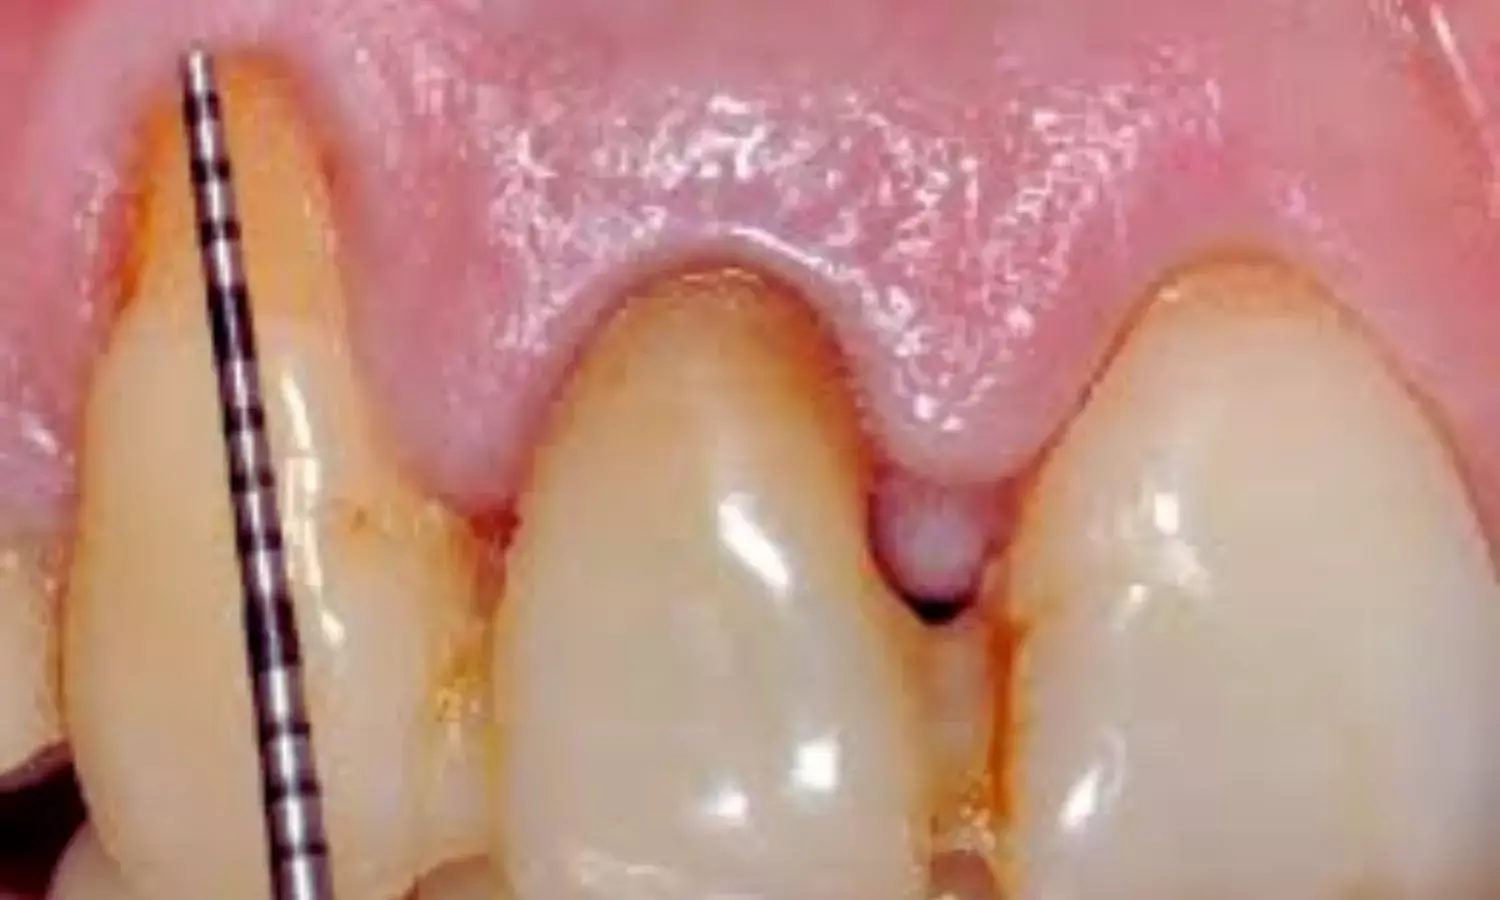

Gingival recession, where the gum margin moves apically and exposes the root surface, is frequently seen in clinical practice. Importantly, nearly half of these cases are associated with NCCLs—tooth structure losses near the gum line that are not caused by decay. When both conditions coexist on the same tooth, they are referred to as

combined defects (CDs)

. These situations are more complex than isolated gingival recession on an intact tooth and often require tailored treatment strategies.